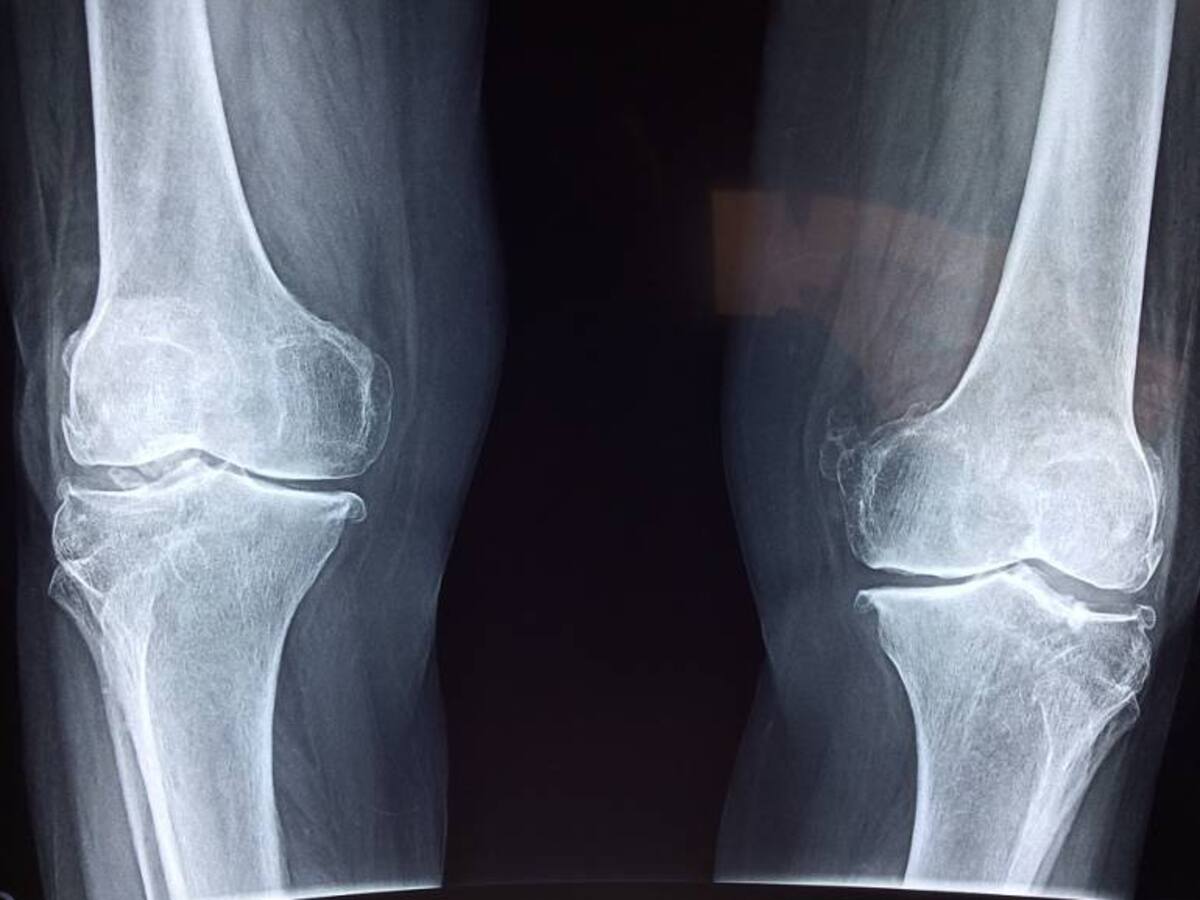

¿Ha perdido talla en su estatura? Puede tener la enfermedad de los huesos

Si ha perdido talla en su estatura o ha empezado a encorvarse, puede estar presentando osteoporosis, una enfermedad silenciosa que debilita los huesos, ¿Cómo reconocer esta enfermedad y cómo prevenirla?